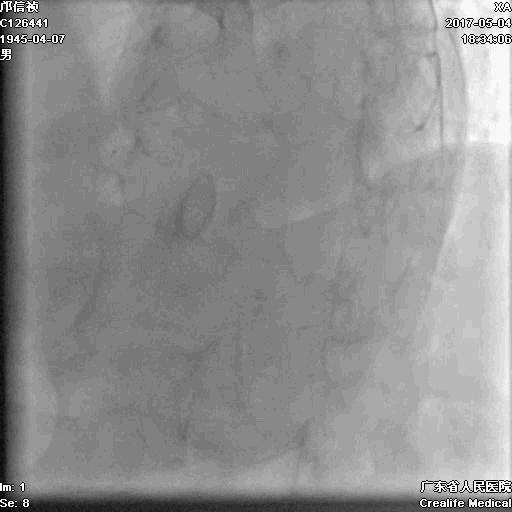

2.5*15mm球囊扩张,逆向导丝尝试,但未能进入正向GC

1.正向2.5*15mm球囊扩张,Reverse CART

2.Guidezilla延长导管辅助下,逆向导丝进入正向GC

1.更换RG3导丝

2.GC送入普通导丝,保护LM